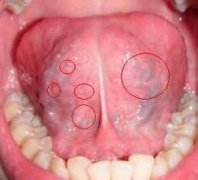

石家庄九州皮肤病医院 > 尖锐湿疣 > > > 口腔感染尖锐湿疣如何治疗比较好呢?尖锐湿疣主要是发生在生殖部位上,但是由于不良性生活方式传染,尖锐湿疣也是可以出现在口腔、腋窝等部位的,虽然口腔患上尖锐湿疣的几率是比较小的,但是也是存在的,对于口腔尖锐湿疣建议患者最好还是能够去科学的诊断治疗,尖锐湿疣只要是能够正确的治疗还是可以根治的,当然对于口腔尖锐湿疣的治疗患者应当是对因对症的治疗才好,可不要盲目的用药,那么口腔感染尖锐湿疣如何治疗比较好呢?